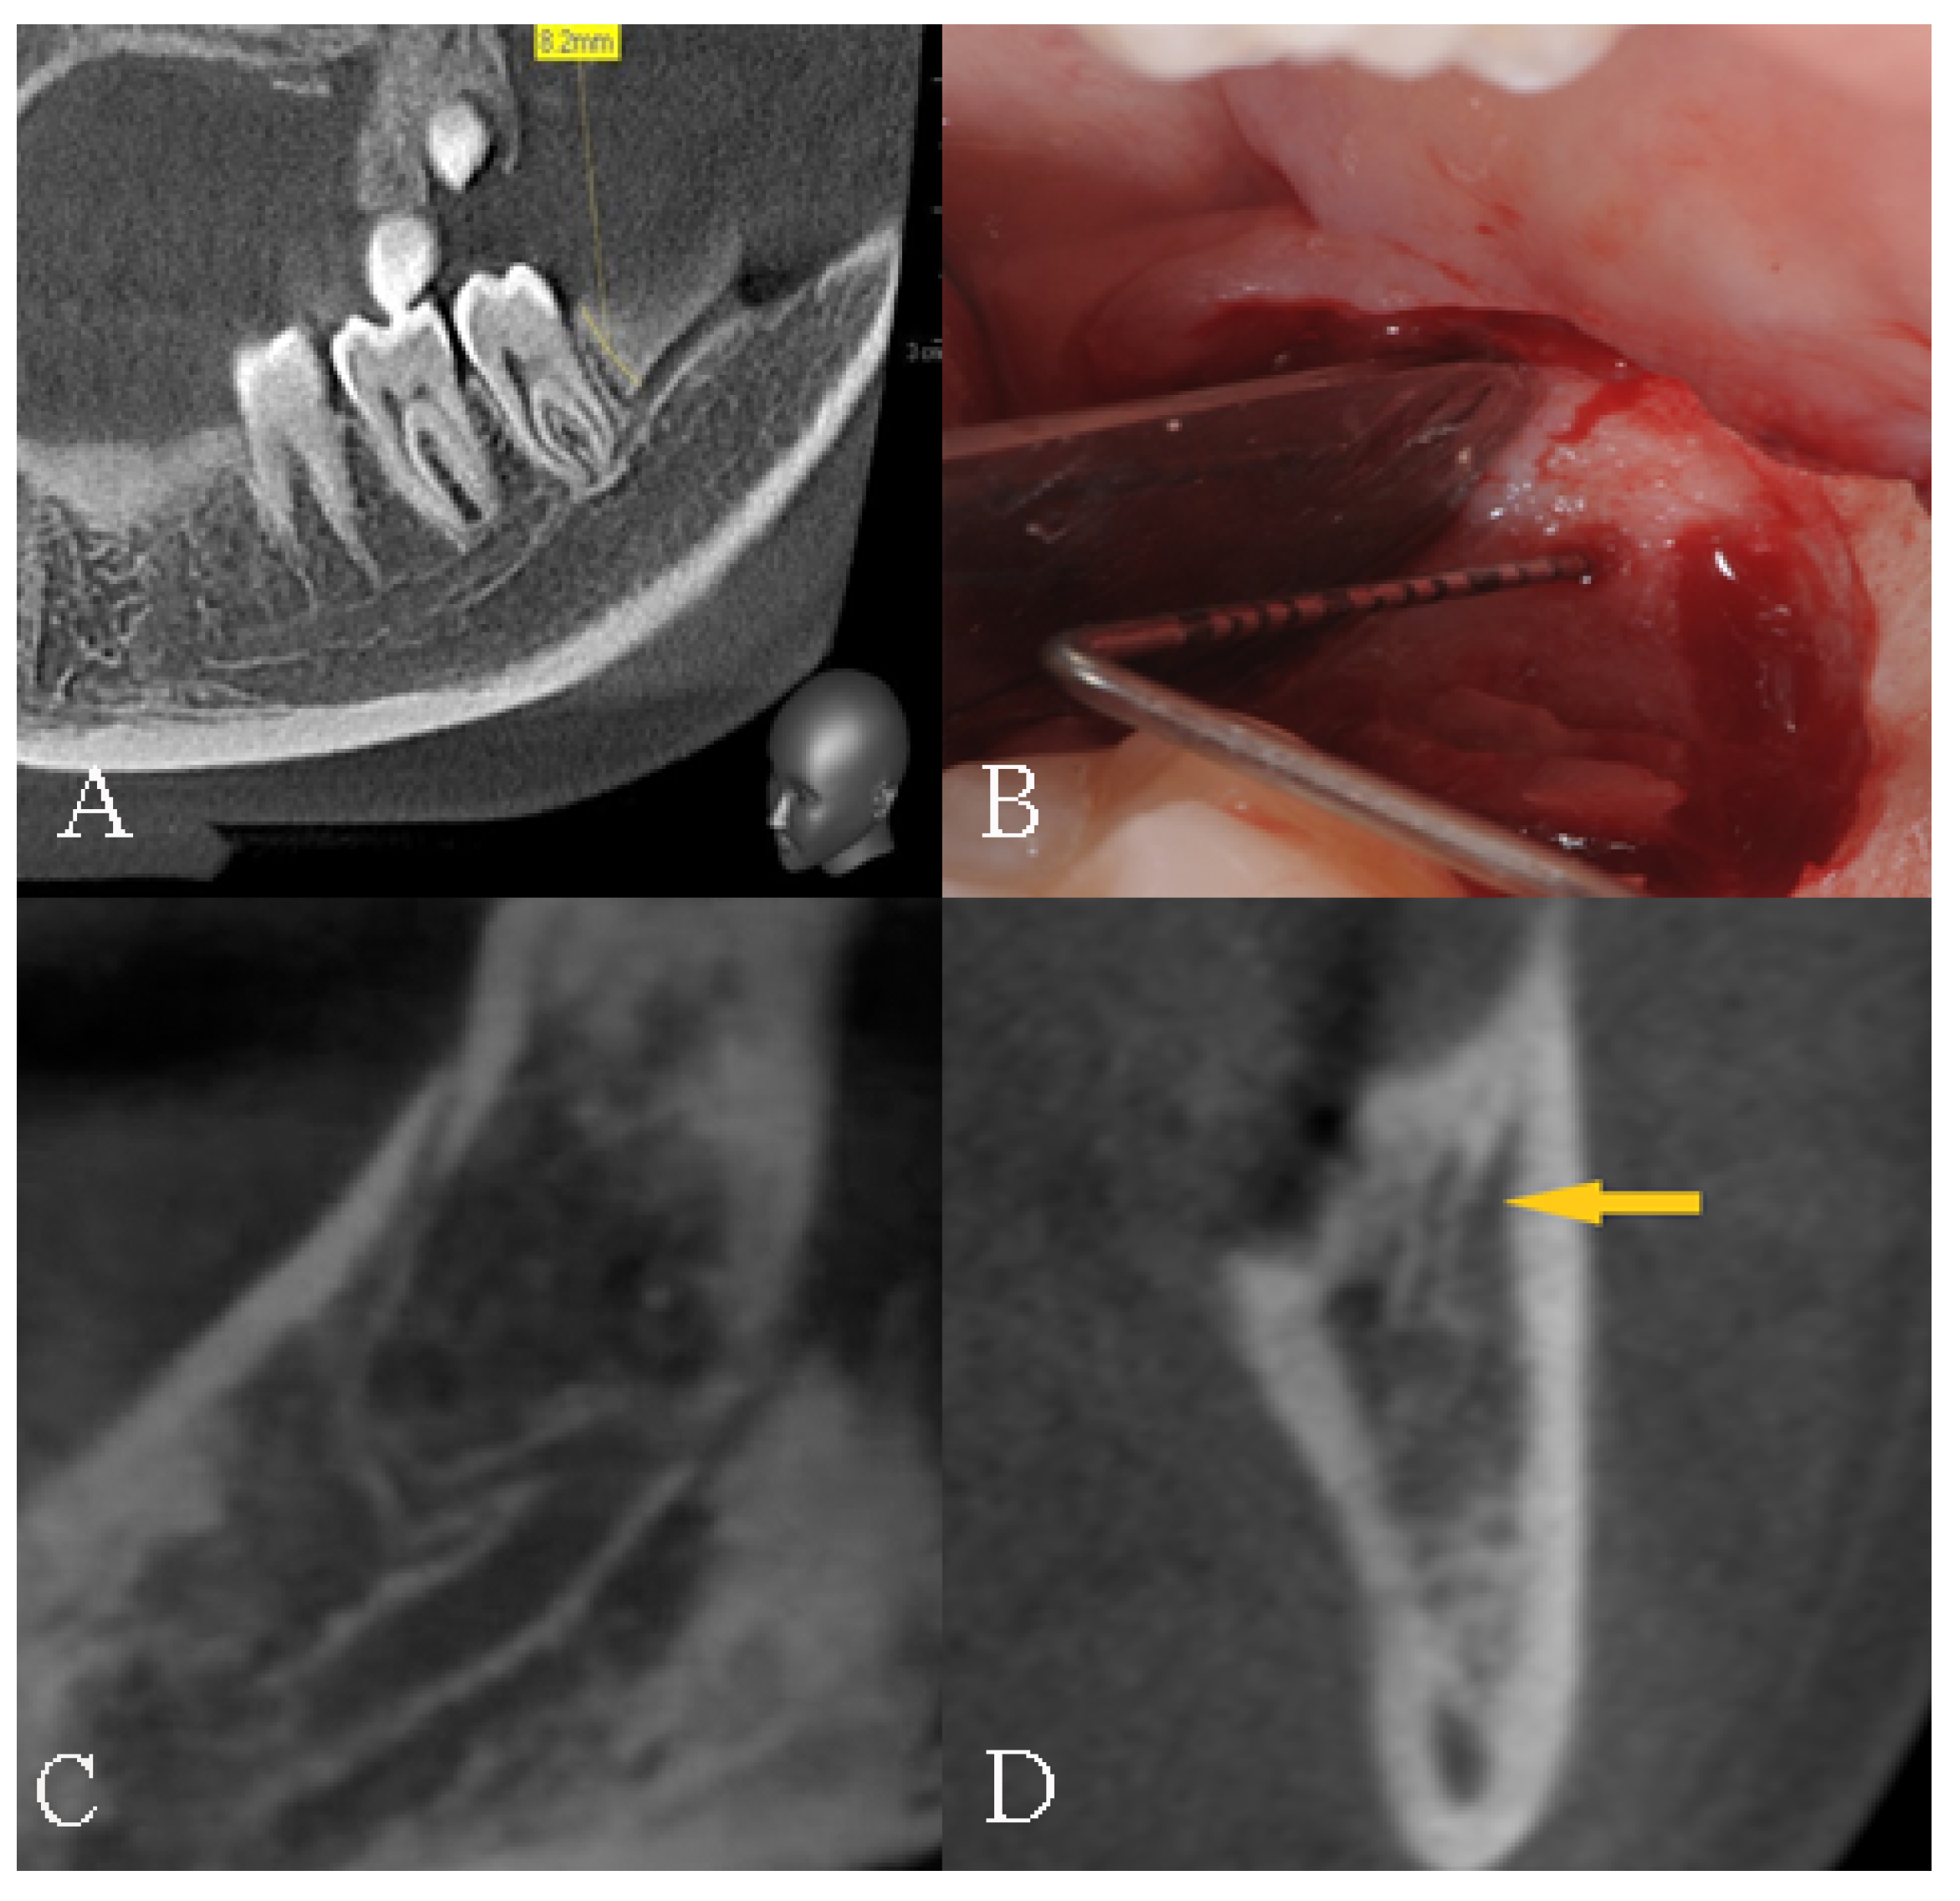

4.1. CBCT as a Reliable Preoperatory Assessment Method